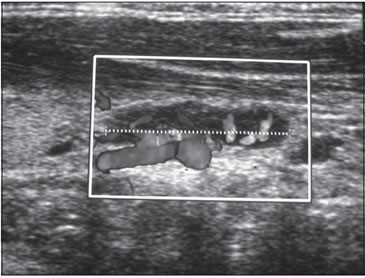

La ecografía cervical de alta resolución, mostró inicialmente

que la estructura glandular tiroidea era heterogénea, y

existía, detrás del polo inferior del lóbulo izquierdo, un nódulo

ovoideo de 14 mm de diámetro, irrigado por una arteriola

independiente (Figura 2). En controles anuales, el nódulo

descrito no presentó variaciones y mantuvo su característica

de independencia vascular.

Figura 2. Ecografía que muestra nódulo retrotiroideo izquierdo de

14 mm x 6 mm. Nótese la presencia de una arteriola que irriga independientemente

la lesión.